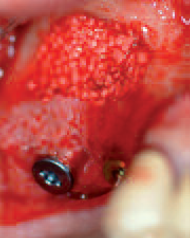

Inserted collagen membrane with perforation of the Schneiderian membrane in region 16 after insertion of implant

nserted implant with buccal bone defect at the level of the implant shoulder